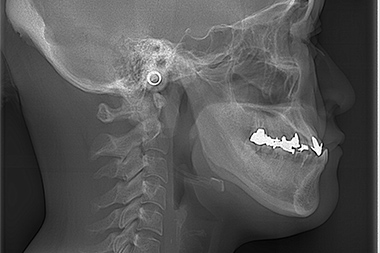

セファロ分析

歯科専用のレントゲンです。矯正治療において分析の根本となるもので、セファロ分析を行うことで口腔内の不正歯列が明らかになります。歯の角度や距離を計測することで、歯の移動の仕方や抜歯の有無などについての判断材料としても有効です。セファロ分析の結果、マウスピース型矯正歯科装置による歯列矯正に向いていない場合もあるので治療を成功させるためにも重要な検査といえます。

セファロ分析により不正歯列を確認

正常な歯列のセファロ分析

正常な歯列

上顎前突のセファロ分析

上顎前突の場合

下顎前突のセファロ分析

下顎前突の場合

お顔全体の写真を撮影することで、「生体が機能できる口元になっているか」「お顔全体のバランスがとれているか」など、多くの情報を得ることができます。また、横顔の美しさの指標として用いられるEラインを確認する手段としても有効です。しっかりと口が閉じられると、お顔全体のバランスが改善されるほか、唾液の乾燥を防ぎ歯周病などの予防にもつながります。口腔内の変化を比較検討できるように治療の節目で撮影を行います。

矯正治療によって

美しいEラインへと改善された例

例えば出っ歯(上顎前突)の患者さんの場合、鼻と顎を点で結んだラインから口が閉じられずにはみ出していることがわかります。これが改善されると高い審美性を得られるほか、生体がしっかりと機能するようになります。口が閉じられないと唾液が乾燥し口腔内の免疫力が低下することで、歯周病リスクが高まり全身への影響を及ぼす可能性があります。